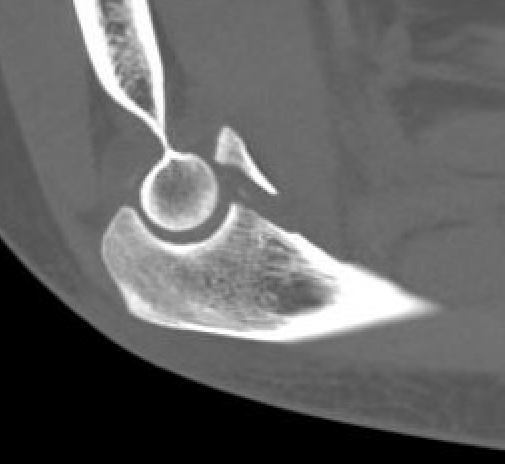

Anteromedial coronoid facet fragment

- associated with varus posteromedial rotational force

- associated with tear of lateral ulna collateral ligament (LUCL)